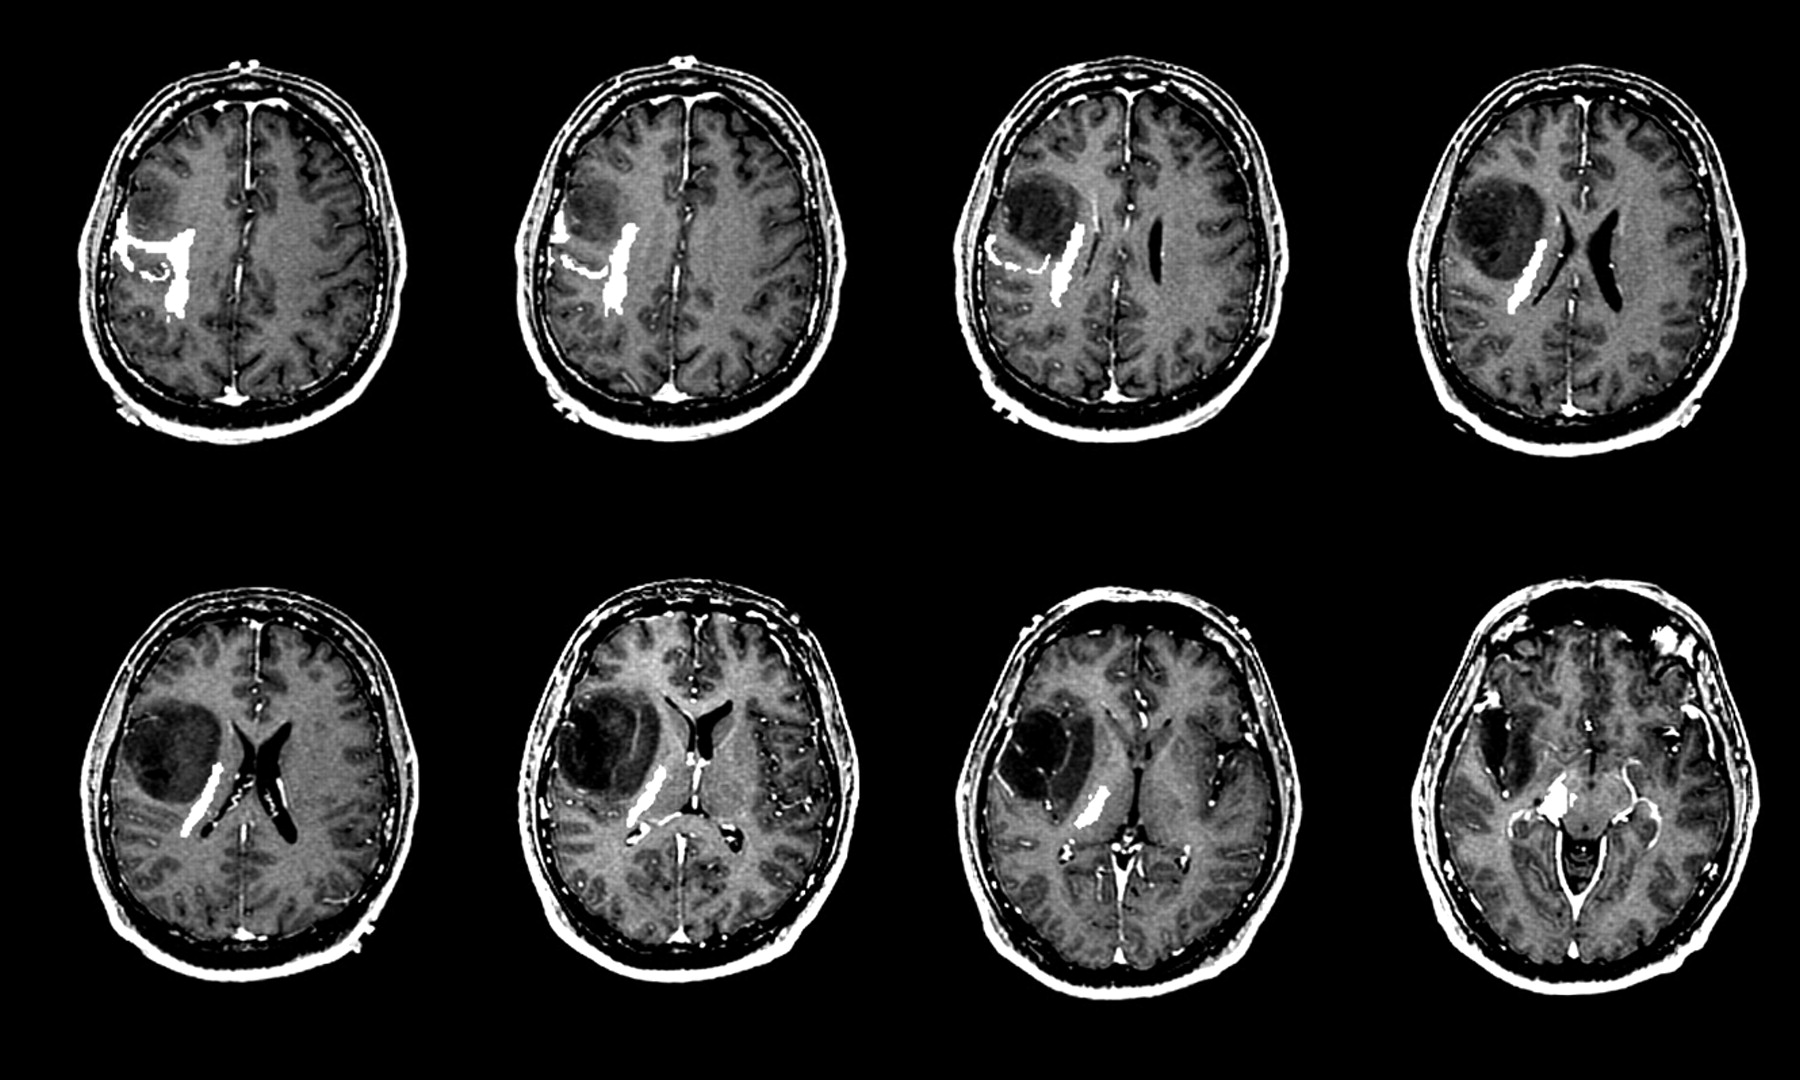

Understand how a shunt in the brain manages hydrocephalus by diverting excess cerebrospinal fluid. This comprehensive guide explains the surgical procedure, common types of ventricular shunts, potential complications, and essential long-term maintenance. Learn how this life-saving medical device improves brain pressure regulation and patient outcomes for those suffering from fluid buildup or increased intracranial pressure.